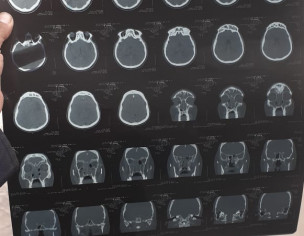

Ct scan report is attached. Doctor suggest for operation. Need 2nd opinion. Patient is worry. Can you plz guide is operation is the solution then what is th procedure for operation. Means behosh kr k krty hain ya sun kr k? Aur is ka operation ziada serious to ni hota ku k dmag aur eyes ki waja sy? Aur ic ka operation kic surgeon sy krana chahiy general ya koi specialist jo b hay bta dein? Aur kehan sy krwaien? Need doctor opinion

There is sinus infection if all sinuses. Functional endoscopic sinus surgery is required to relieve the symptoms.